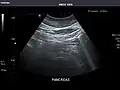

Pancreas -

Pancreas: Visualized portions unremarkable.